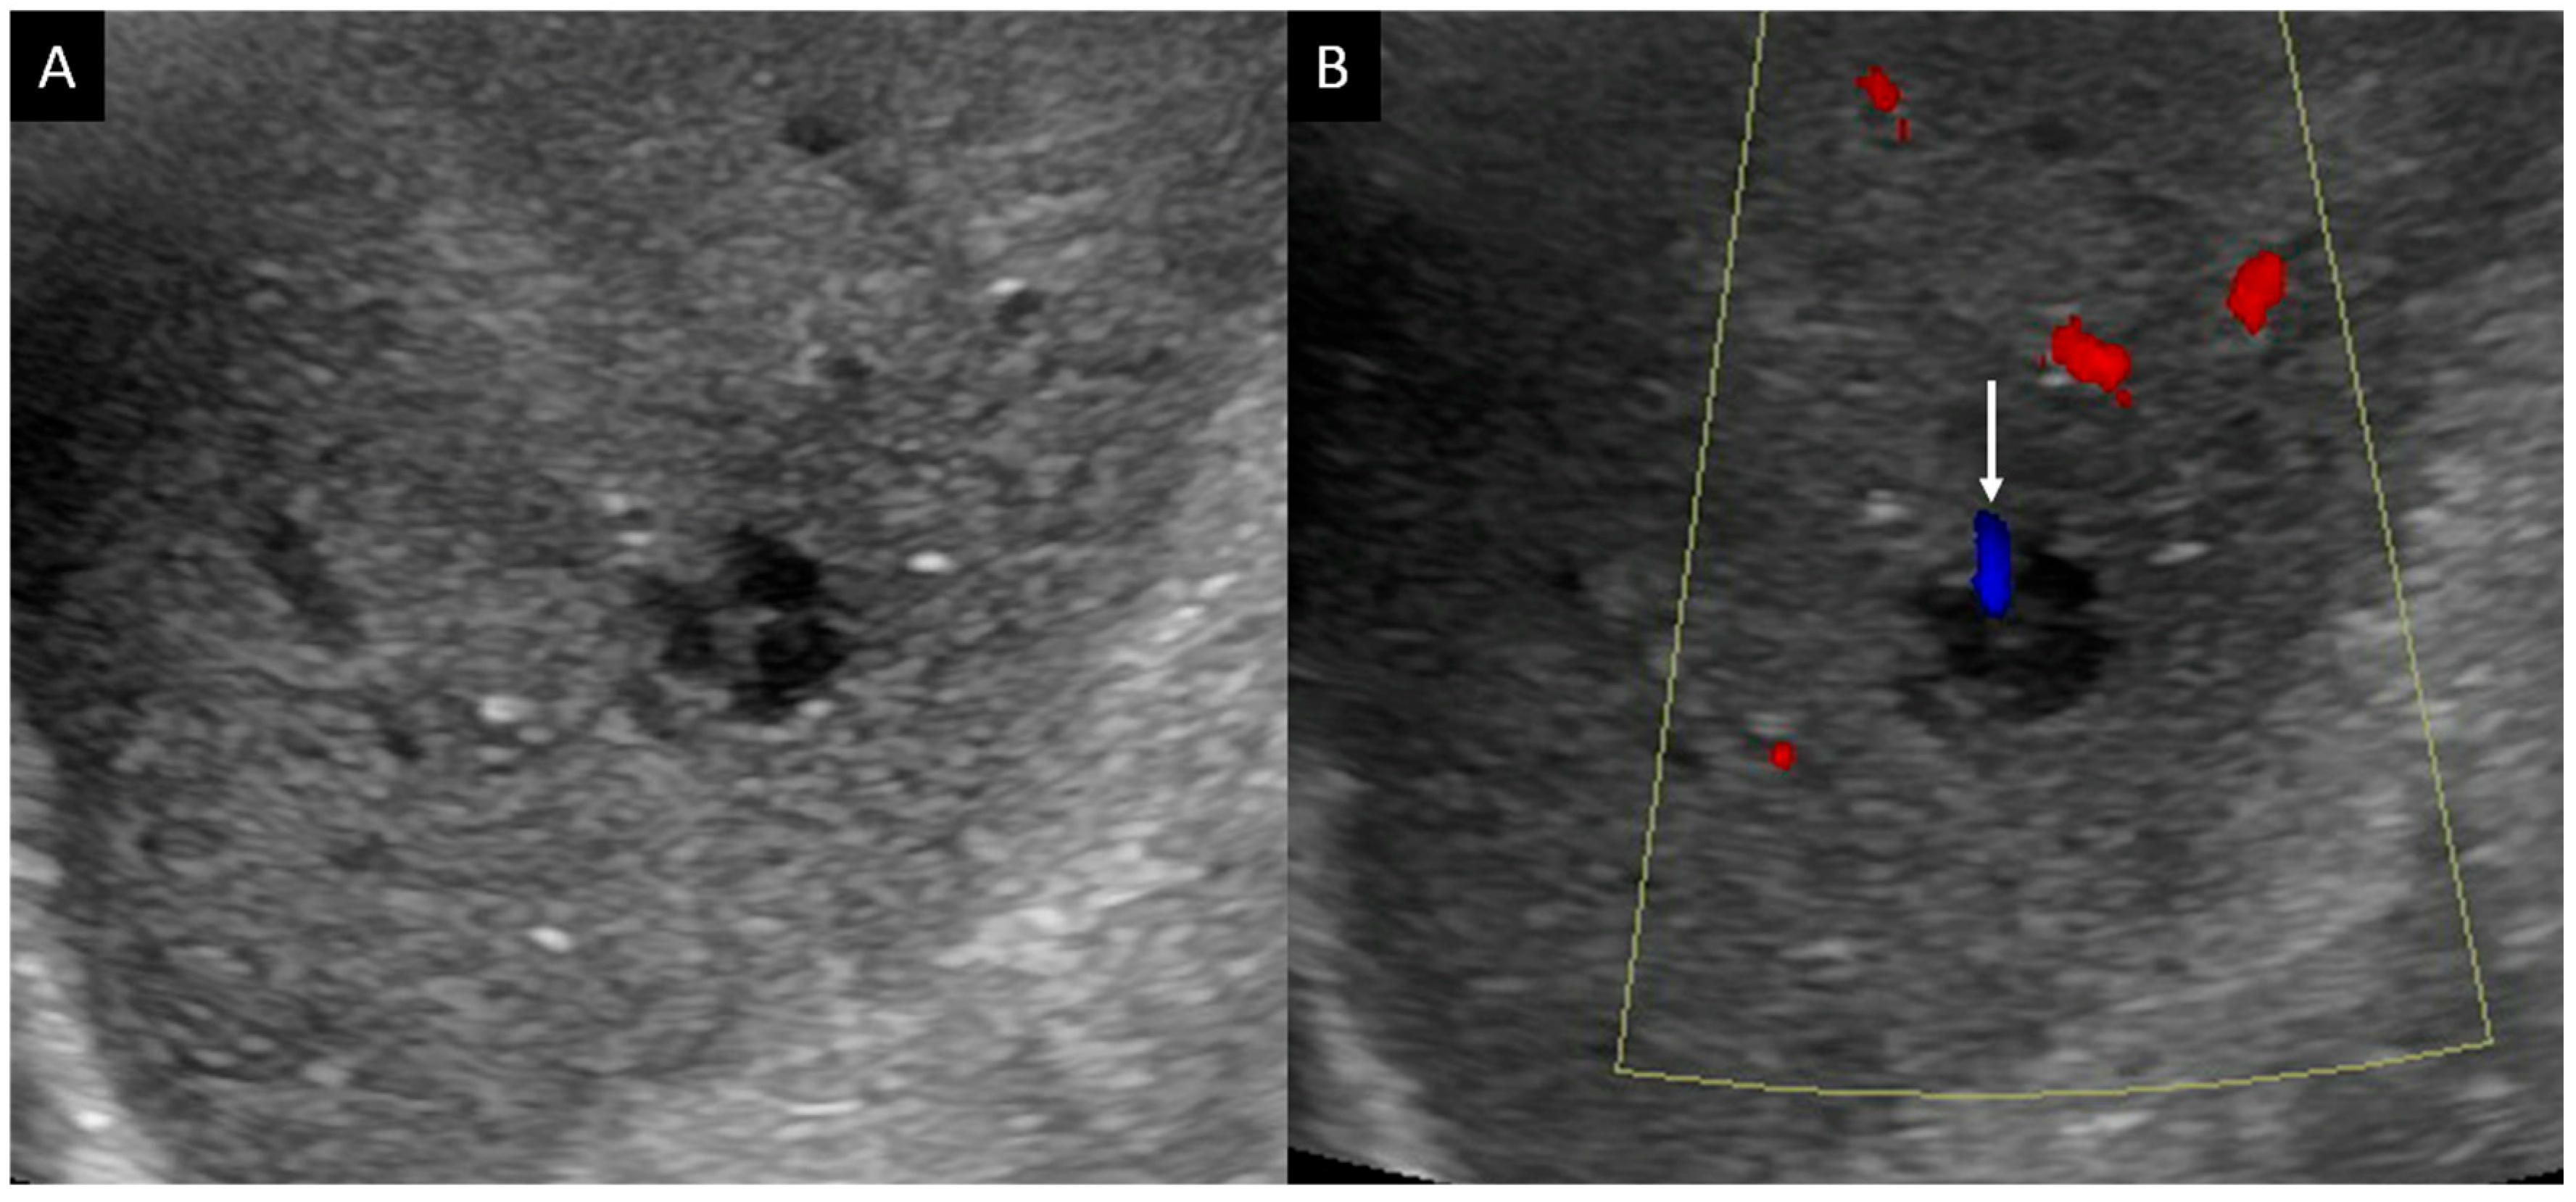

- He, M.-N.; Lv, K.; Jiang, Y.-X.; Jiang, T.-A. Application of superb microvascular imaging in focal liver lesions. World J. Gastroenterol. 2017, 23, 7765–7775. [Google Scholar] [CrossRef] [PubMed]